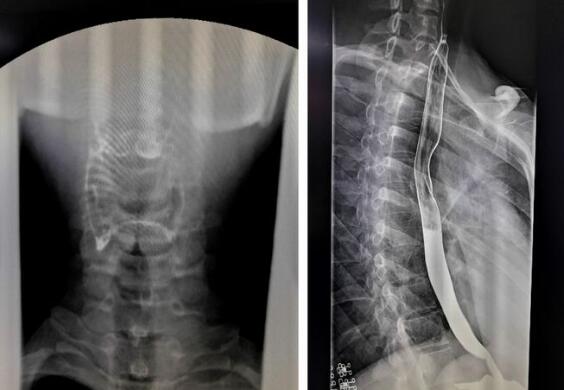

數(shù)字化胃腸機(jī)拍攝的上消化道造影圖

隨著數(shù)字化胃腸機(jī)臨床應(yīng)用越來越廣泛,其功能性也大大增強(qiáng),那么數(shù)字化胃腸機(jī)到底能做哪些檢查呢?其功能你有了解多少?1、上消化道造影,能顯示咽部到十二指腸的影像。